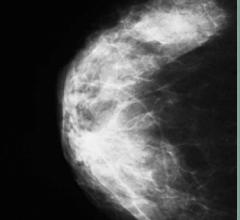

Looking for signs of cancer in the mammogram of a dense breast is like looking for a polar bear in a snowstorm. Because they absorb X-rays, glandular and fibrous tissue appear white, as do microcalcifications, lumps and other lesions that may indicate breast cancer.

The practice of breast imaging and screening in women at risk for breast cancer is evolving as new imaging modalities are incorporated and researchers continue to study the implications of dense breast tissue in patients. At the 2013 annual meeting of the Radiological Society of North America (RSNA) in Chicago, there were several sessions highlighting trials and studies that brought breast density and cancer detection to the forefront.